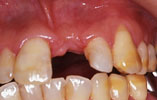

CASE2

上の前歯4本が欠損 審美的回復

インプラント埋入前

インプラント埋入後

インプラントに

セラミッククラウンを装着

上の前歯4本が欠損しており、以前は義歯が入っていました。3本のインプラントを埋入して、固定のブリッジを装着しました。口元のコンプレックスも解消されました。